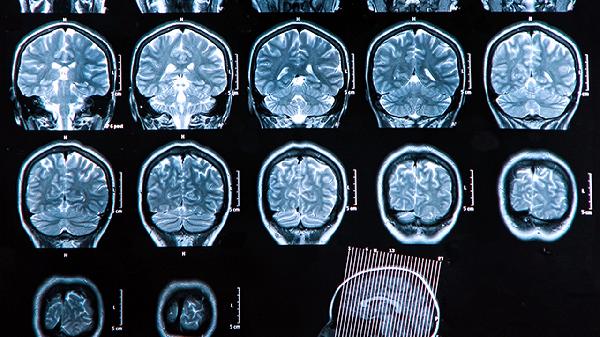

不同部位CT检查的辐射剂量差异显著。头部CT单次有效剂量约2毫西弗,而腹部或盆腔CT可达10毫西弗。高剂量部位短期内重复检查需更谨慎评估。